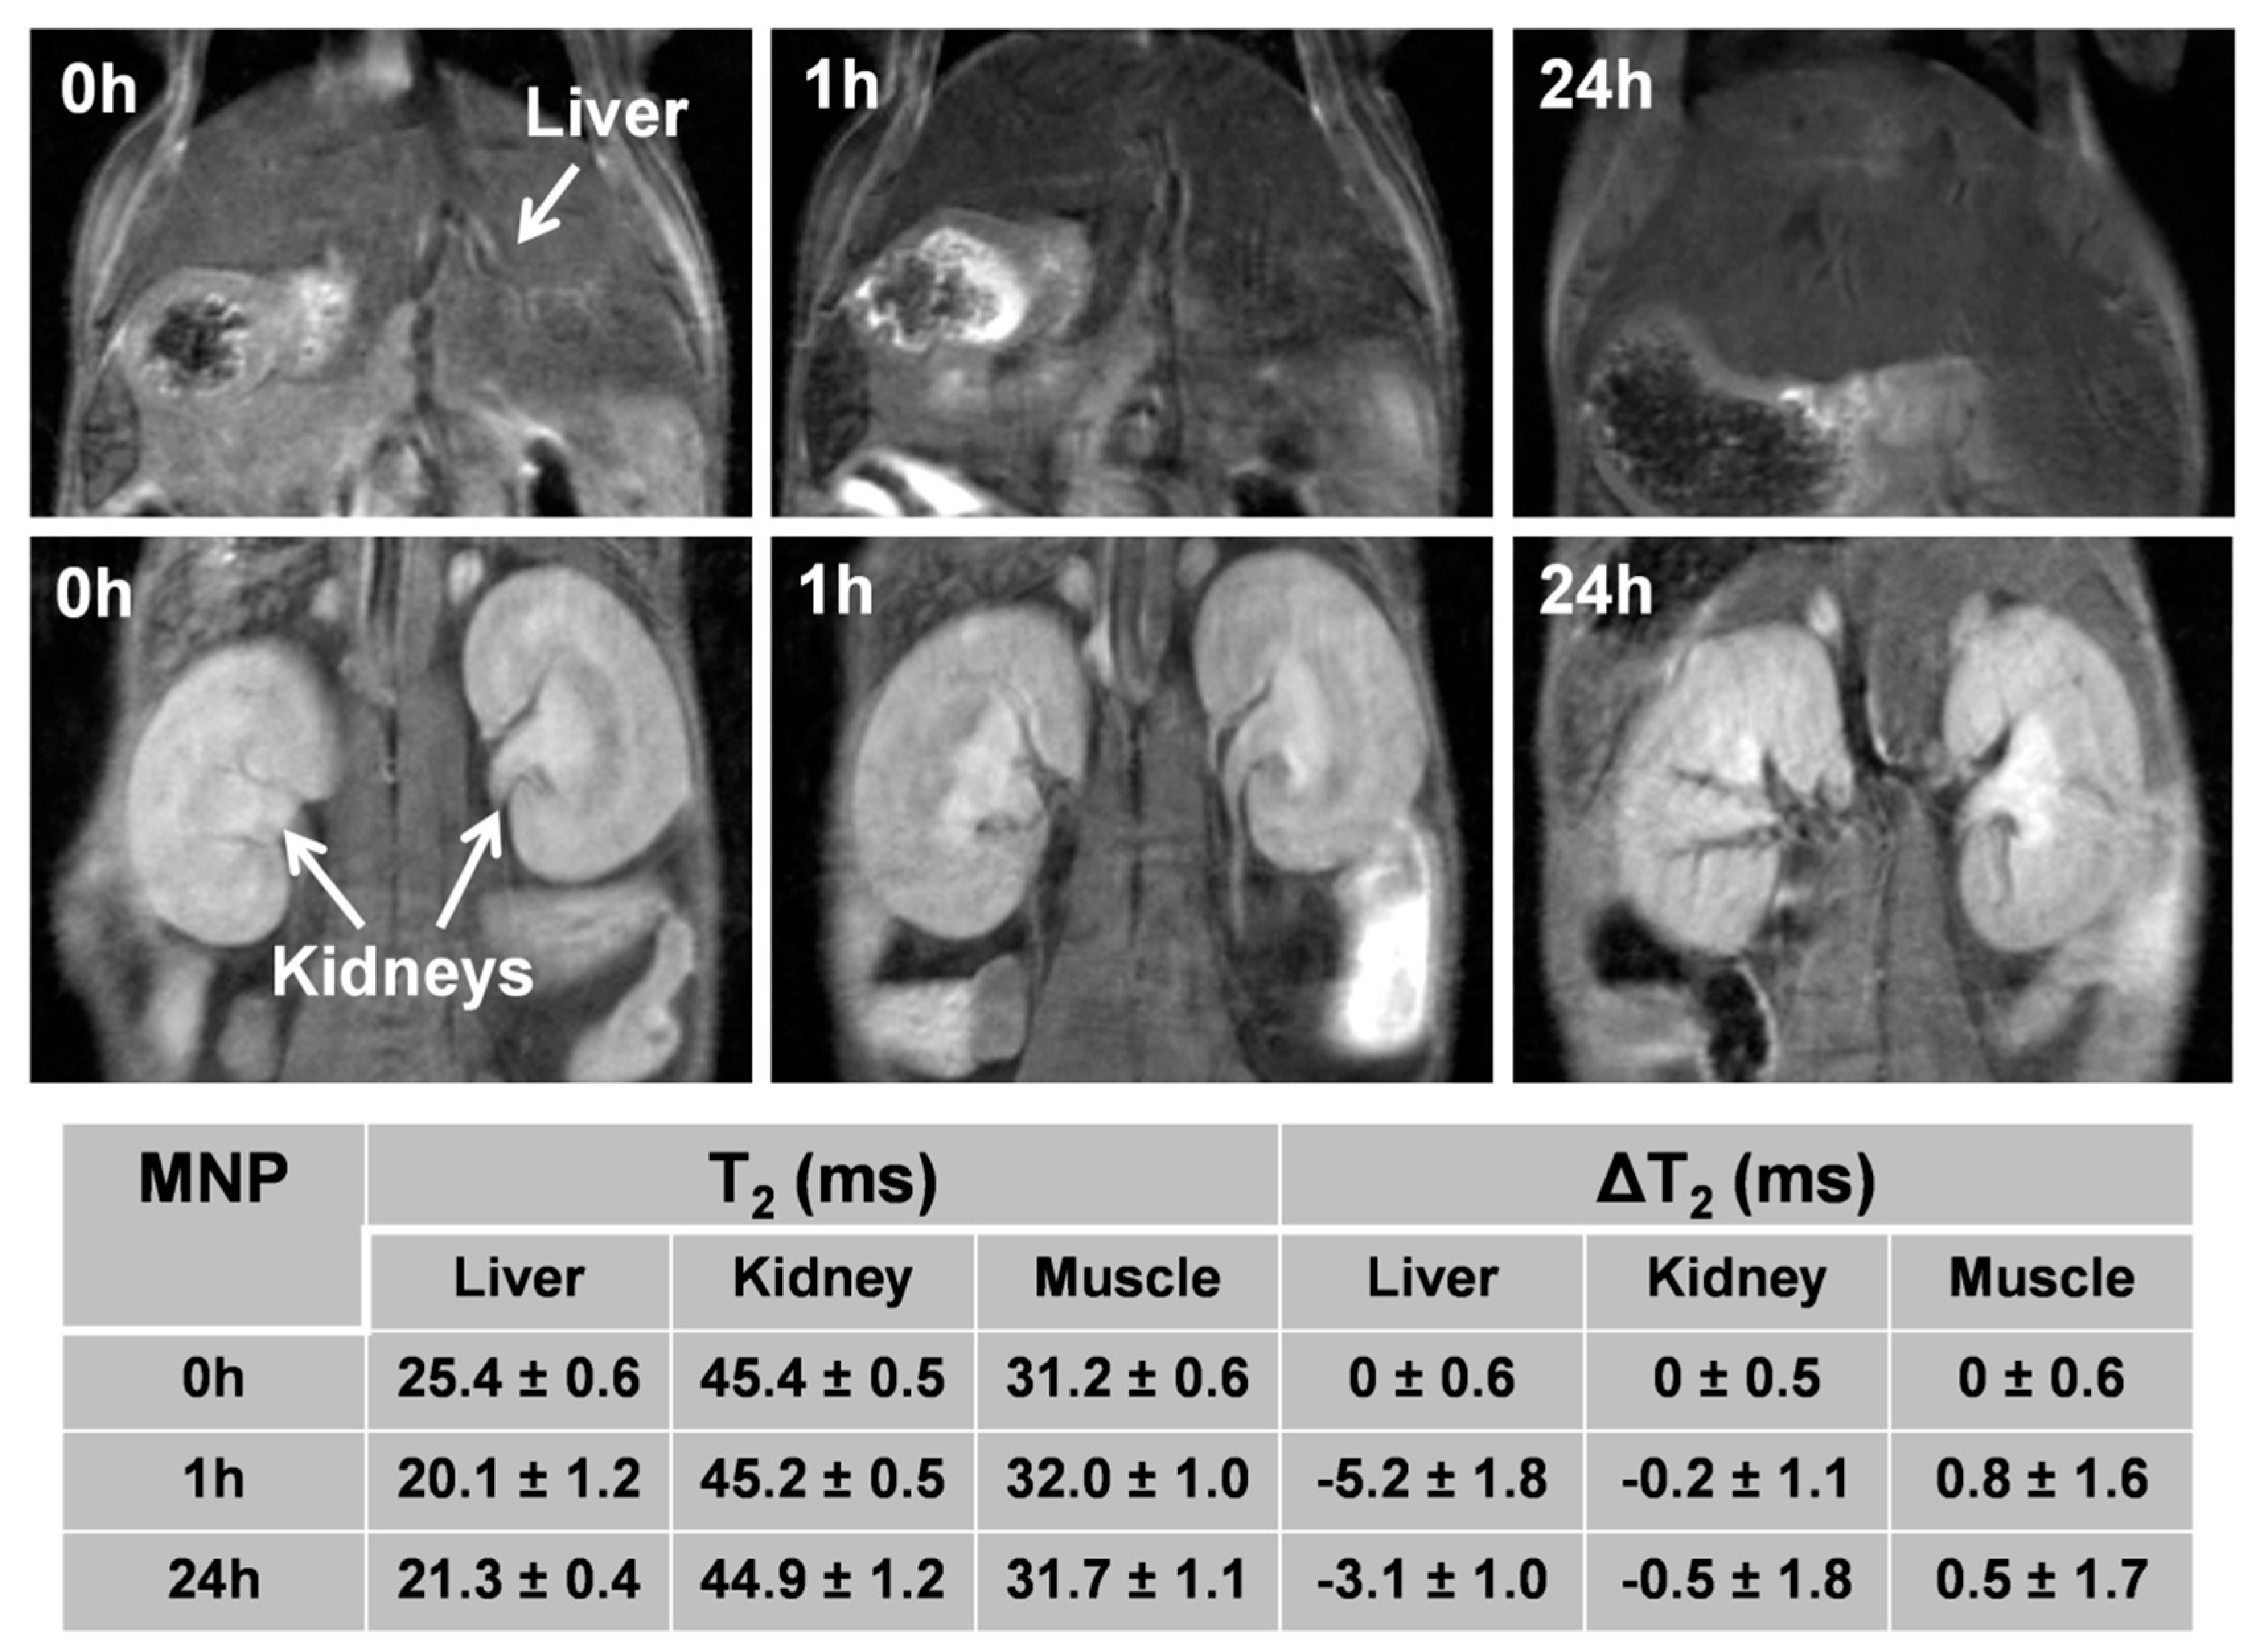

3.8. In Vivo MRI Studies